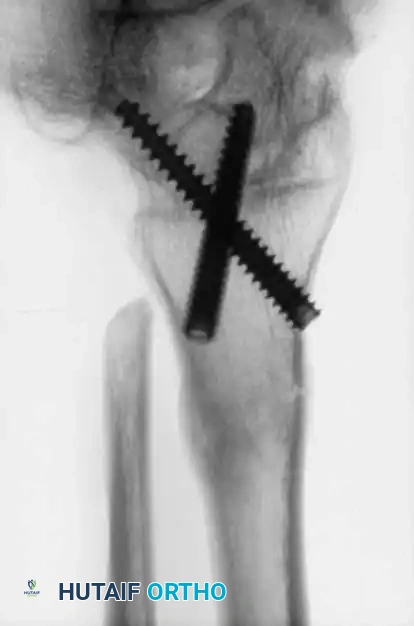

Image

Advanced hemophilic arthropathy of the ankle often requires aggressive intervention. When arthroscopic synovectomy fails to control symptoms in end-stage disease, definitive stabilization via ankle arthrodesis utilizing rigid internal fixation becomes necessary to eliminate pain and prevent further hemorrhagic episodes.